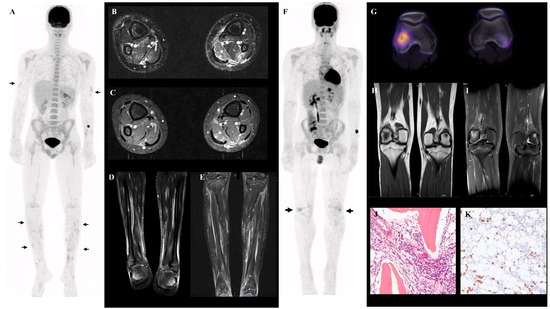

MRI images of the lower limbs, contemporaneous (within 7 days) to PET-CT, were acquired in two patients (patients 3 and 4), both positive for the aforementioned PET-CT findings (Figure 2A). In both, MRI confirmed diffuse, patchy T2-hyperintense signal localized in the muscles and subcutaneous tissue (Figure 2B–E).

Figure 2. (A) FDG PET-CT MIP of patient 3, showing patchy hypermetabolic foci in the limbs, predominantly in the legs (arrows). (BD) Axial and coronal MRI of the lower legs of patient 3, showing patchy and diffuse muscular and subcutaneous hypersignal (T2FS sequence in (B,D), T1 FS in (C)). (E) Axial MRI of the lower legs of patient 4, showing patchy and diffuse muscular and subcutaneous hypersignals (T1 FS). (F) FDG PET-CT MIP of patient 4, demonstrating increased bone uptake in both lateral femoral condyles (thick arrows). (G) Fused transverse FDG PET-CT views of the bone lesions in the lateral femoral condyles, with underlying lytic lesions. (HI) MRI imaging showing T1 hypointense (T1 TSE sequence in (H)), and T2 hyperintense (T2 SPAIR sequence in (I)) aspects of the bone lesions. (J,K) Bone biopsy (right femoral condyle) of patient 4, demonstrating plasmocytic infiltrate and mild medullary fibrosis (Hematoxylin eosin staining in (J) and anti-CD138 staining in (K) (brown)).

Two patients (2 and 4) also displayed bone abnormalities. Patient 4 had three hypermetabolic bone lesions (both femoral lateral condyles and sternum (Figure 2F–G and Supplementary Figure S1A)), with an SUVmax of 5.5. The right lateral femoral condyle lesion showed moderate lysis on CT. On MRI, the lesions were T1 hypointense and T2 hyperintense (Figure 2H–I). Biopsy was suggestive of chronic aseptic osteomyelitis (plasmocytic infiltrate and mild medullary fibrosis, Figure 2J–K). The second patient with abnormal bone PET-CT was found to have a hypermetabolic (SUVmax 5.1) pelvic bone lesion (Supplementary Figure S1B).